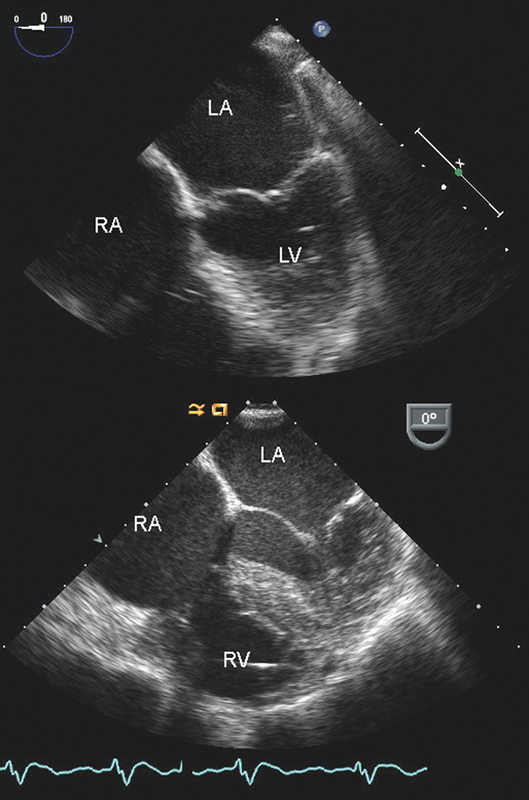

فحوصات تشخيصية لبعض امراض القلب والشرايين التاجية